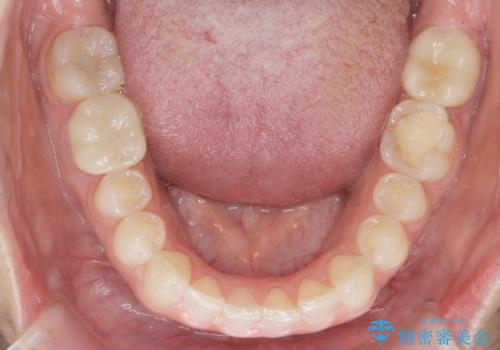

下の前歯のちょっとしたがたつきを治したい

- 下の前歯のがたつきを治したいとのことでした。

下の歯並びを並べるため、わずかに歯を削合しています。

そうしないと、前に出て上の前歯に強く当たってしまうためです。また、後戻りを防ぐ効果もあります。